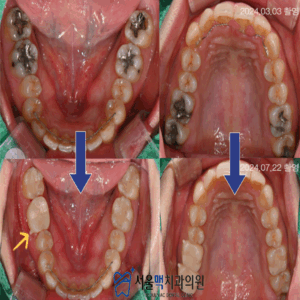

처음 내원하셨을 때 구강 내 촬영한 모습입니다.

화살표로 표시된 부분이 오래전에

아말감으로 충치치 료를 받으신 치아인데요.

아말감은 금속을 바탕으로한

재료로 시간이 지나면

부식되면서 색이 어둡게 변하는데요.

게다가 우식부분을 제거하고

아말감을 충전할 때,

접착제를 쓰지 않기때문에 사진에서처럼

일부가 조각으로 떨어져 나가는 경우도 있습니다.

환자분의 경우는

아말감으로 치 료한 아래치질이 검게 보이며

2차충치가 있으셨구요,

치아에 금이 간 부분도 있으셨어요.

이전에 아말감과 2차적으로

발생한 우식을 제거하였을 때,

범위가 컸기때문에 다시 떼우는(충전하는) 방식의

치료는 어려웠습니다.

그래도, 가능한 자연치질을 많이 남겨서

치료해드리기 위해 크라운(Crown)과

인레이(Inlay)로 충치치료를 마무리 해드렸는데요 ~

서울맥치과의 섬세함으로

전보다 자연스러운 치아색으로 마무리되어

환자분께서 몹시 기뻐하셨어요:)

노란색 화살표를 보시면,

크라운 보철물 볼쪽으로 작은 돌기가

나와있는 것을 보실 수 있는데요.

보철물이 완성되면 임시로

약 1주이상 사용해보시고 재부착해드리는데,

다시 재부착 하기위해 크라운을 빼는

문고리 같은것이라고 생각하시면 됩니다.

영구접착 해드릴 때는 제거해드리니

걱정하시마시고,

편하게 사용해보시고 말씀해주세요 🙂